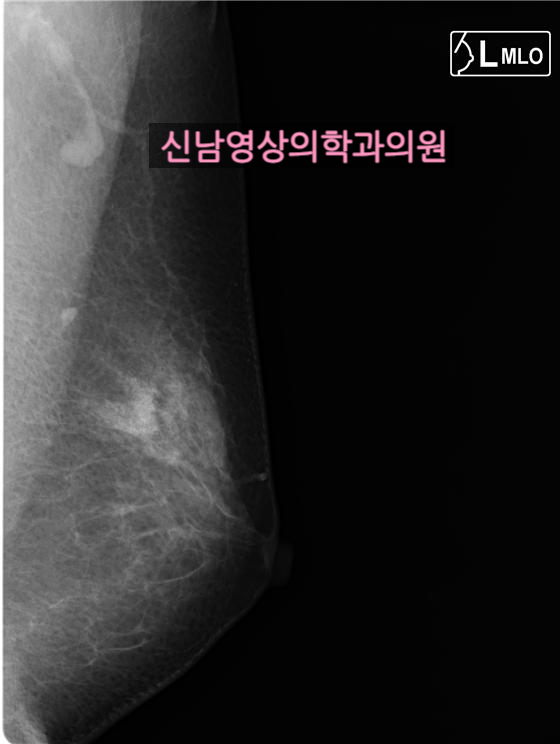

본원에서 유방 촬영, 유방 초음파를 시행한 50대 여성의 사례 |

비대칭 증가음영으로 사진상 미세석회화도 동반되어 있었습니다.

초음파상 이 부위에 종괴가 있었고, 총생검상 상피내암으로 진단 받고, 수술 후 0기암으로 최종 진단을 받았습니다.